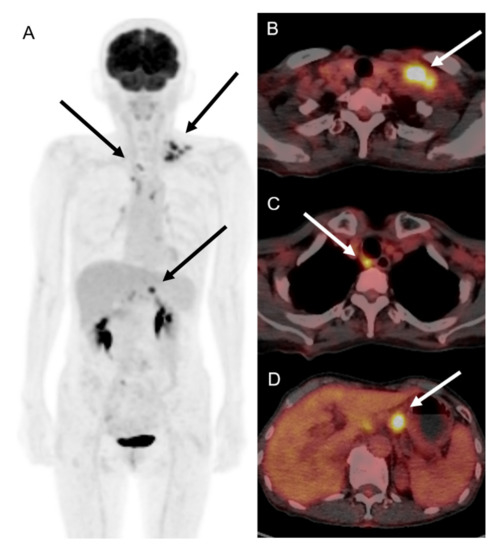

Figure 3.

18F-FDG PET/CT images of patient with COVID-19 vaccination-induced lymphadenopathy patient. Maximum intensity projection (A) and tomographic axial images of 18F-FDG PET/CT showed multiple hypermetabolism in left supraclavicular (B), retrotracheal (C), and left gastric artery lymph nodes (D), with maximum standardized uptake value of 5.1–9.5.

A 66-year-old female patient visited the outpatient clinic complaining of prolonged ipsilateral supraclavicular LN enlargement that emerged 3 days after she received the second dose of the ChAdOx1 (Oxford-AstraZeneca) vaccine on her left deltoid muscle (Figure 1 and Table 1). She only had injection site tenderness and fatigue after the first vaccination. She was a housewife who had no history of recent traveling or meetings due to the pandemic. She had recovered from acute idiopathic thrombocytopenic purpura 3 years previously and had no other underlying disease. No additional symptoms including fever, cough, myalgia, or weight loss were observed. Vaccine-induced adverse reactions were assumed, and the patient’s condition was carefully monitored. There was no change in the size of the enlarged LN 8 weeks after vaccination without any abnormal laboratory findings (white blood cell count 7830 mm3, neutrophil 66.4%, lymphocyte 21.4%, and platelet count 214,000 mm3); however, ultrasonography revealed multiple enlarged LNs, with conglomeration in the left supraclavicular area (Figure 2). 18F-FDG PET/CT was performed to rule out primary malignancy metastasis. In the results, the 18F-FDG PET/CT images revealed multiple hypermetabolic LNs not only in the left supraclavicular area but also in the paratracheal, right hilar, and anterior diaphragmatic areas as well as left gastric, periportal, gastroepiploic, and paraaortic areas. There were no hypermetabolic lesions in both lungs (Figure 3). LN biopsy revealed chronic granulomatous inflammation of the supraclavicular area, with caseous necrosis that was consistent with TB. Real-time polymerase chain reaction (PCR) revealed Mycobacterium tuberculosis as the causative agent and the enlarged LN started to diminish after the initiation of rifampin, isoniazid, pyrazinamide, and ethambutol therapy.

Ultrasonography may be the most simple and non-invasive diagnostic tool in cases of extrapulmonary TB with LN enlargement. Typical sonographic features of TB lymphadenitis are multiple, irregular, enlarged, and conglomerating lymph nodes that have a tendency toward fusion [25], which is the exact finding in our case. 18F-FDG PET/CT can also contribute to earlier extrapulmonary TB detection particularly in multisite involvement cases with an average maximum standardized uptake value (SUVmax) of 5.3–13.4 [26,27]. Multiple hypermetabolism has an SUVmax of 5.1–9.5 in cases where the patient presents a typical characteristic of extrapulmonary TB in 18F-FDG PET/CT. Another simple option prior to biopsy for screening would be the tuberculin skin tests, for which positive results should be further confirmed by in vitro enzyme immunoassay tests [28].